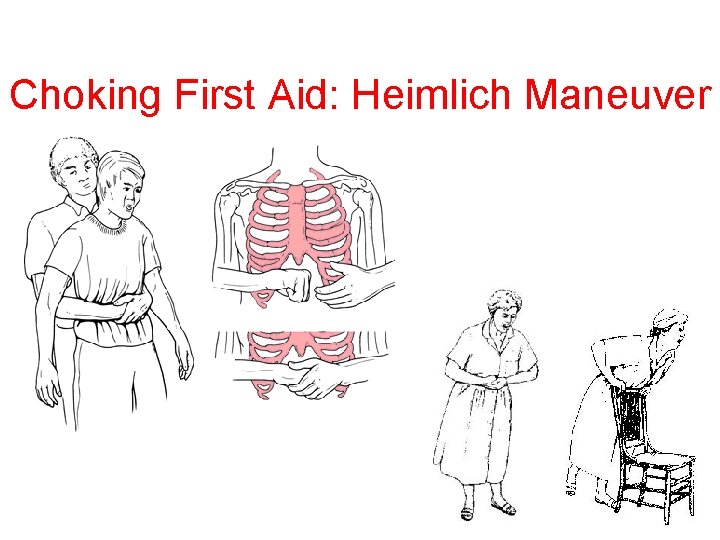

Blocked Airway

Choking First Aid: Heimlich Maneuver